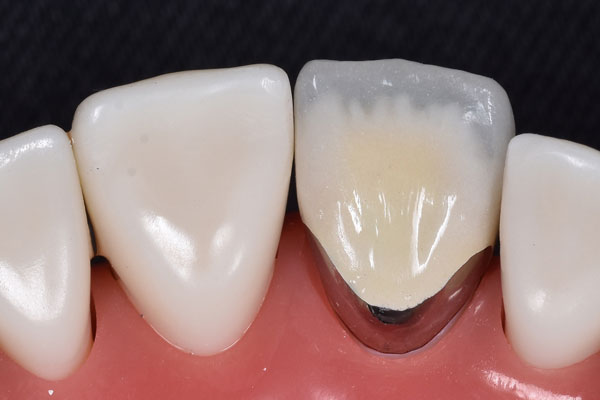

治療前

治療後

年齢・性別 33歳・男性

主訴 虫歯治療がしたい

治療内容 右上56根管治療後ファイバーコア、ジルコニアステインの形成

治療期間 約2ヶ月

費用 ジルコニアステイン110,000円×2

合計:220,000円

治療リスク・

副作用

色展開が6色のみ、天然の歯よりも硬い